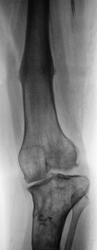

Явления артрита налицо - узурация суставной поверхности наружного быщелка БК, его остеосклероз и кистозная перестройка. Деформация ББК диспластическая (?), может ФКД. Аппарат был вероятно не калссическим Идизарова - след от внедрения в ББК схож со стержнем, а не спицей. Блаунт, да еще после аппаратной коррекции должен восстановиться до примерно нормального мыщелка.

в диафизе бедренной и метадиафизе большеберцовой вероятно результат остеотомии для коррекции

Складывается впечатление, уважаемый Валентин Львович, что в Вашем районе не только все переломы по-пьяни, но и лечение болезни Блаунта. Ось конечности почти восстановили, но кто же додумался исправлять варус голени за счет вальгуса бедра?